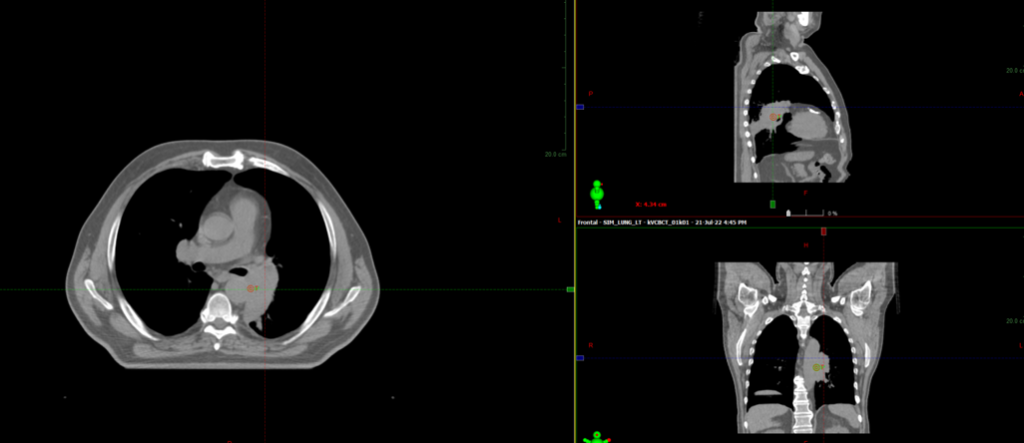

Во время СВСТ при первом сеансе ЛТ выявлен ателектаз левого легкого

CBCT - конусно-лучевая компьютерная томография, ЛТ – лучевая терапия

22.07.2022г. выполнена повторная

КТ- топометрия органов грудной клетки

С 25.07.2022 начат курс лучевой терапии

На аппарате HALCYON с ежедневной KV-визуализацией

В Институте ядерной медицины мы регулярно используем ежедневную KV-визуализацию (компьютерная томография с коническим пучком) для более точной локализации опухоли и проведения прецизионной, то есть суперточной лучевой терапии. Особенно важна ежедневная визуализация при раке легкого, когда объем облучения может значительно и быстро изменяться, в результате резорбции опухоли или вследствие осложнений, например ателектаза. Так же ежедневная визуализация позволяет уменьшить отступ на погрешность в укладке пациента, тем самым снижает лучевую нагрузку на критические органы

СВСТ от 8.08.2022

CBCT - конусно-лучевая компьютерная томография

08.08.2022 на СОД 22 Гр выполнена повторная

КТ- топометрия органов грудной клетки

Курс химиолучевой терапии продолжен по плану